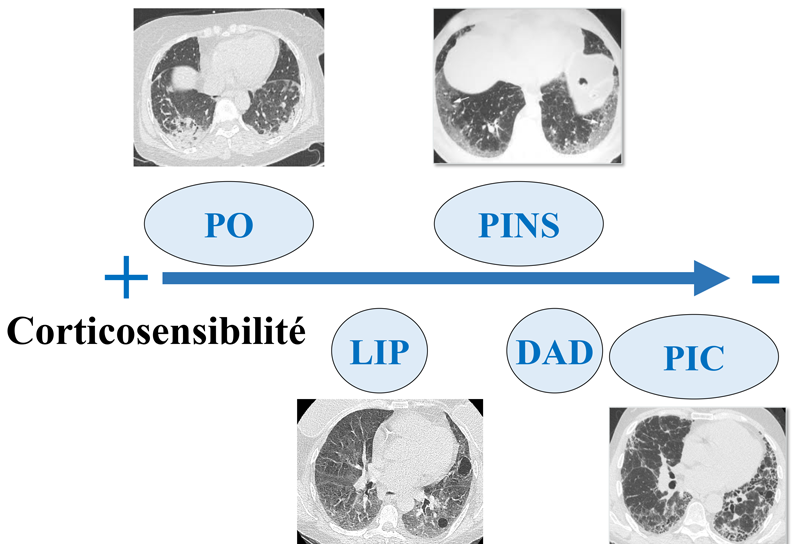

Le diagnostic des PID repose sur une première étape de recherche étiologique. Vient ensuite, l’analyse de l’aspect de la PID qui va permettre de guider le traitement. En effet l’aspect de la PID est prédictif de la réponse aux immunosuppresseurs et en particulier au corticostéroïdes (Figure 2). Ainsi un aspect de pneumopathie organisée (PO) est en règle générale associé à une très bonne réponse aux corticostéroïdes. À l’inverse, un aspect de pneumopathie interstitielle commune (PIC) n’est pas associé à une amélioration fonctionnelle sous corticostéroïdes. La mise en évidence d’un aspect de PIC dans un contexte idiopathique permet le diagnostic de FPI et justifie d’un traitement antifibrosant (cf infra).

Figure 2 Corticosensibilité prévisible en fonction de l’aspect de la pneumopathie interstitielle diffuse. Pneumopathie organisée (PO), pneumopathie interstitielle lymphocytaire (LIP), Pneumopathie interstitielle non spécifique (PINS), Dommage alvéolaire diffus (DAD), Pneumopathie interstitielle commune (PIC).